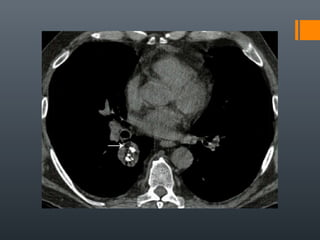

O documento discute vários conceitos radiológicos incluindo consolidação, atelectasia, nódulos, pseudocavidades e padrões intersticiais, fornecendo definições, sinais e diagnósticos diferenciais para cada tópico. Ele também discute a redução da atenuação pulmonar e fornece um link para mais informações.